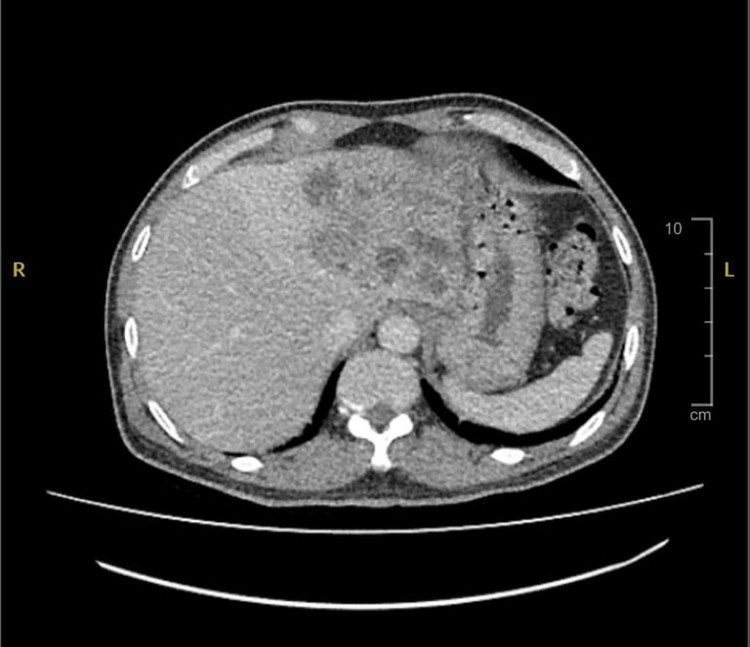

| Hình ảnh CT phát hiện gan bị tổn thương - Ảnh BVCC |

Tại Bệnh viện Đa khoa Xuyên Á, các bác sĩ đã thăm khám và chỉ định cho ông L. chụp CT. Kết quả ghi nhận thùy trái gan có nhiều hốc sỏi, ủ dịch mủ, toàn bộ nhu mô gan thùy gan trái bị xơ teo, mất chức năng toàn bộ, viêm đường mật, sỏi gan trái trên nền bệnh đái tháo đường, có rối loạn đông máu.